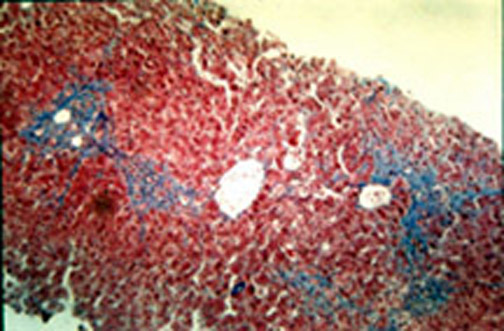

8-4-6.jpg (64481 bytes)  Fig.8-4-6.

In this case,  there is beginning portal, periportal andporto-central fibrosis. The case is lonstanding, more than 8 years under amiodarone treatment.